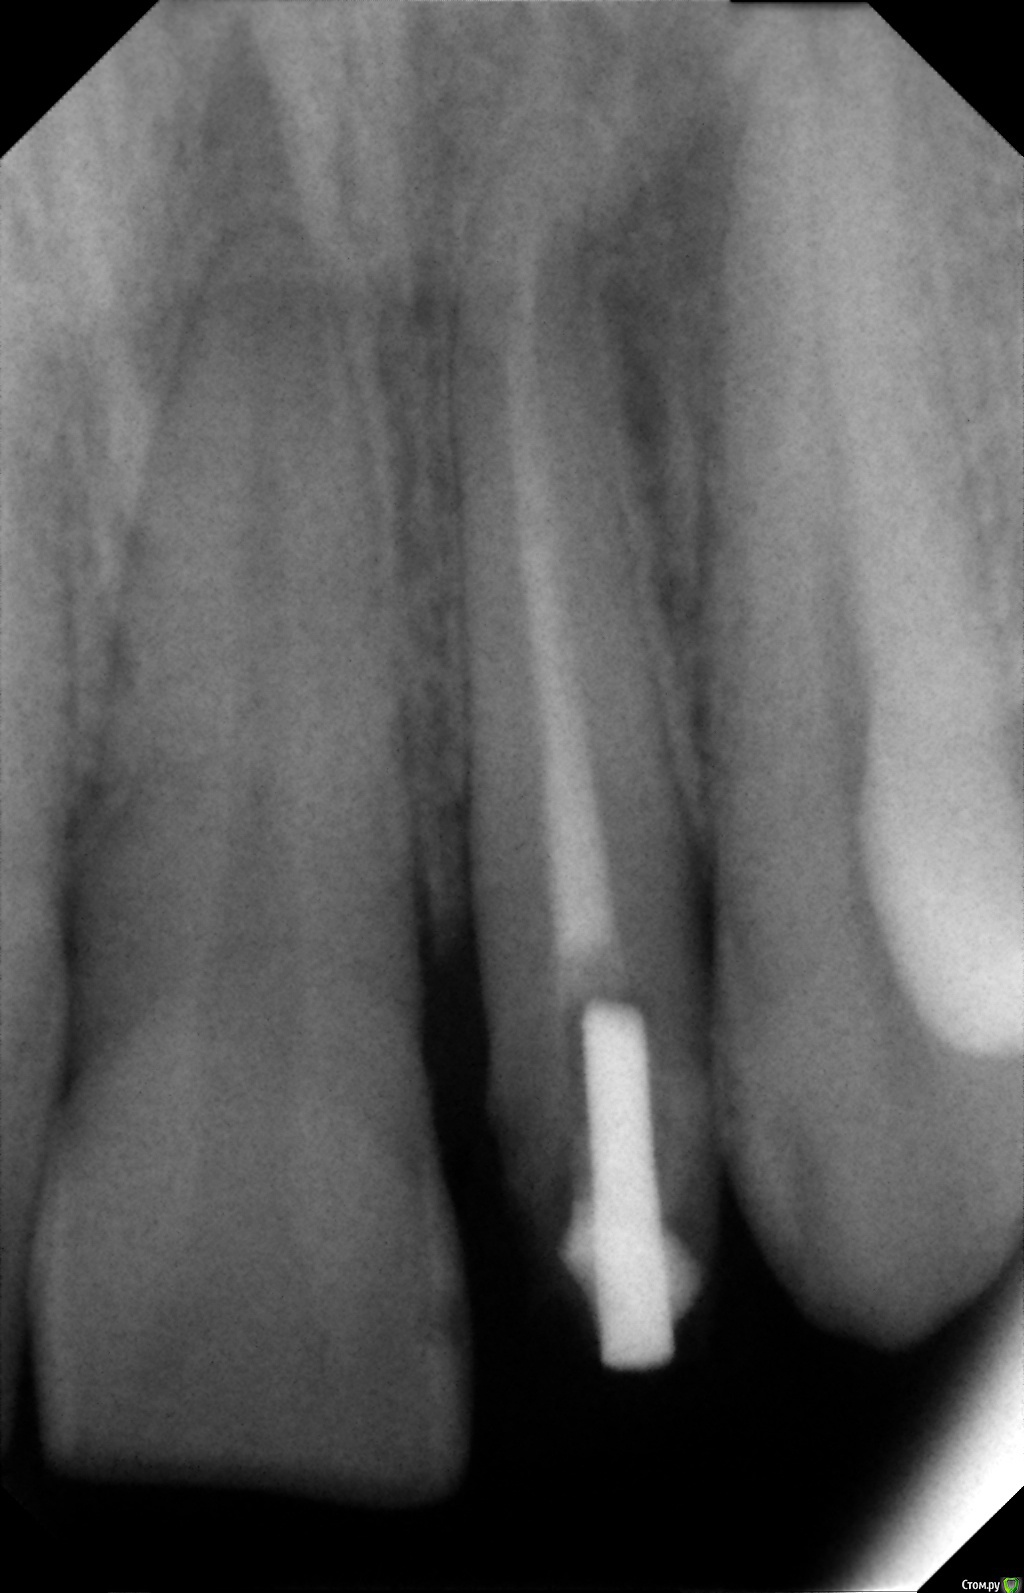

LARIEL Опубликовано 9 мая, 2015 Поделиться Опубликовано 9 мая, 2015 Нужна консультация специалистов. Город маленький, выбирать не из чего. Какие перспективы у зуба со штифтом? Предлагается поставить пластмассовую коронку на то, как есть сейчас на снимке, если металлокерамику - поменять штифт на новый. Ссылка на комментарий

Гарриевич Опубликовано 9 мая, 2015 Поделиться Опубликовано 9 мая, 2015 В идеале:Штифт убрать, зуб перелечить, вкладкой или штифтом восстановить и покрыть коронкойПластмассовая коронка это путь в никуда 3 Ссылка на комментарий

4ebstom Опубликовано 14 мая, 2015 Поделиться Опубликовано 14 мая, 2015 Извлечь штифт,перелечить канал,коронка с восстановлением зуба . Ссылка на комментарий